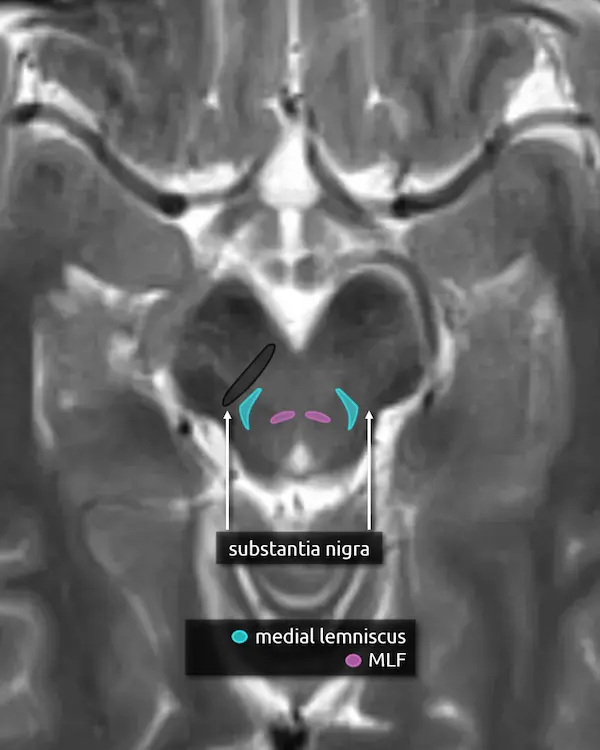

1. Cerebral peduncles

2. Inferior colliculi

3. Decussation of the superior cerebellar peduncles

4. Substantia nigra

5. Medial lemniscus

6. Medial longitudinal fasciculus (MLF)

The substantia nigra is a large nucleus at the base of the cerebral peduncle that spans the midbrain. It is a major component of the extrapyramidal motor system and has bidirectional connections between the striatum (caudate and putamen), forming the nigrostriatal pathway. It is composed of two areas: the pars compacta and the pars reticulata.

Loss of dopamine producing neurons in the pars compacta is a defining feature of Parkinson's disease.

The medial lemniscus is an ascending sensory pathway that spans the entire brainstem, originating at the nucleus gracilis and cuneatus (see level 5) in the medulla and ending at the primary sensory nucleus of the thalamus: the ventral posterolateral nucleus (VPL). It begins medially in the medulla and becomes more lateral at the level of the midbrain, located in close proximity to the substantia nigra. It is responsible for vibration sensation, fine touch, and proprioception.

Lesions involving the medial lemniscus may cause contralateral loss of vibration sensation and joint position sensation on physical exam with symptoms of numbness and paresthesias.

The MLF is an ascending and descending pathway responsible for coordinating eye movements. It connects all of the cranial nerve nuclei that innervate the extraocular muscles (CN III, IV, and VI) as well as the vestibulocochlear nuclei (CN VIII). The MLF spans the entire brainstem, however lesions producing visual symptoms will probably be in the midbrain or pons.

There are characteristic syndromes that result from damage to the MLF, most commonly internuclear ophthalmoplegia (INO) or INO-plus syndromes. A common clinical scenario is a patient with multiple sclerosis who develops a demyelinating lesion along the MLF in the midbrain or pons and presents with bilateral INO.